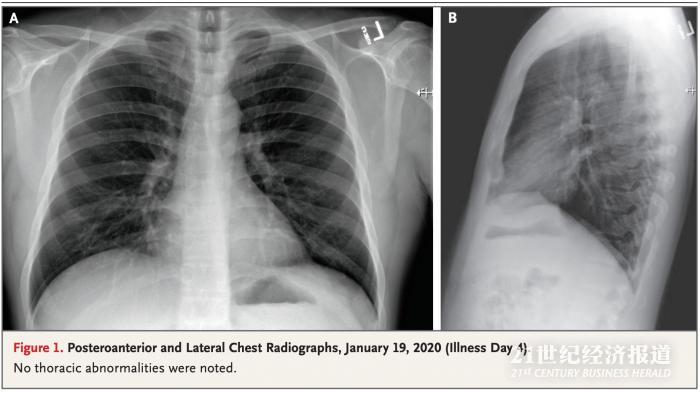

2020年1月19日(疾病第4天)的后前胸和外侧胸片。

除了有高甘油三酸酯血症的病史外,该患者是不吸烟的健康人群。患者体温为37.2°C,血压为134/87 mm Hg,脉搏为每分钟110次,呼吸频率为每分钟16次,氧饱和度为96%。肺部听诊显示有支气管炎,并进行了胸片检查,未显示异常。